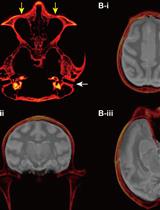

通过手持式注射将化学遗传学腺相关病毒载体靶向递送至猕猴皮质沟区域

Targeted Delivery of Chemogenetic Adeno-Associated Viral Vectors to Cortical Sulcus Regions in Macaque Monkeys by Handheld Injections

KO Kei Oyama

YN Yuji Nagai

TM Takafumi Minamimoto

1699 Views

Dec 5, 2023

Recent advancements in chemogenetic tools, such as designer receptors exclusively activated by designer drugs (DREADDs), allow the simultaneous manipulation of activity over a specific, broad brain region in nonhuman primates. However, the introduction of DREADDs into large and complexly shaped cortical sulcus regions of macaque monkeys is technically demanding; previously reported methods are time consuming or do not allow the spatial range of expression to be controlled. In the present report, we describe the procedure for an adeno-associated viral vector (AAV2.1) delivery via handheld injections into the dorsolateral prefrontal cortex (Brodmann’s area 9/46) of macaque monkeys, with reference to pre-scanned anatomical magnetic resonance images. This procedure allows the precise delivery of DREADDs to a specific cortical region.Key features• This article describes the procedures for injecting viral vectors encoding functional proteins for chemogenetic manipulation into targeted cortical sulcus regions.• The protocol requires magnetic resonance imaging for the accurate estimation of the injection sites prior to surgery.• Viral vector solutions are injected using a handheld syringe under microscopic guidance.• This protocol allows for the precise introduction of designer receptors exclusively activated by designer drugs (DREADDs) to large and complex cortical regions.